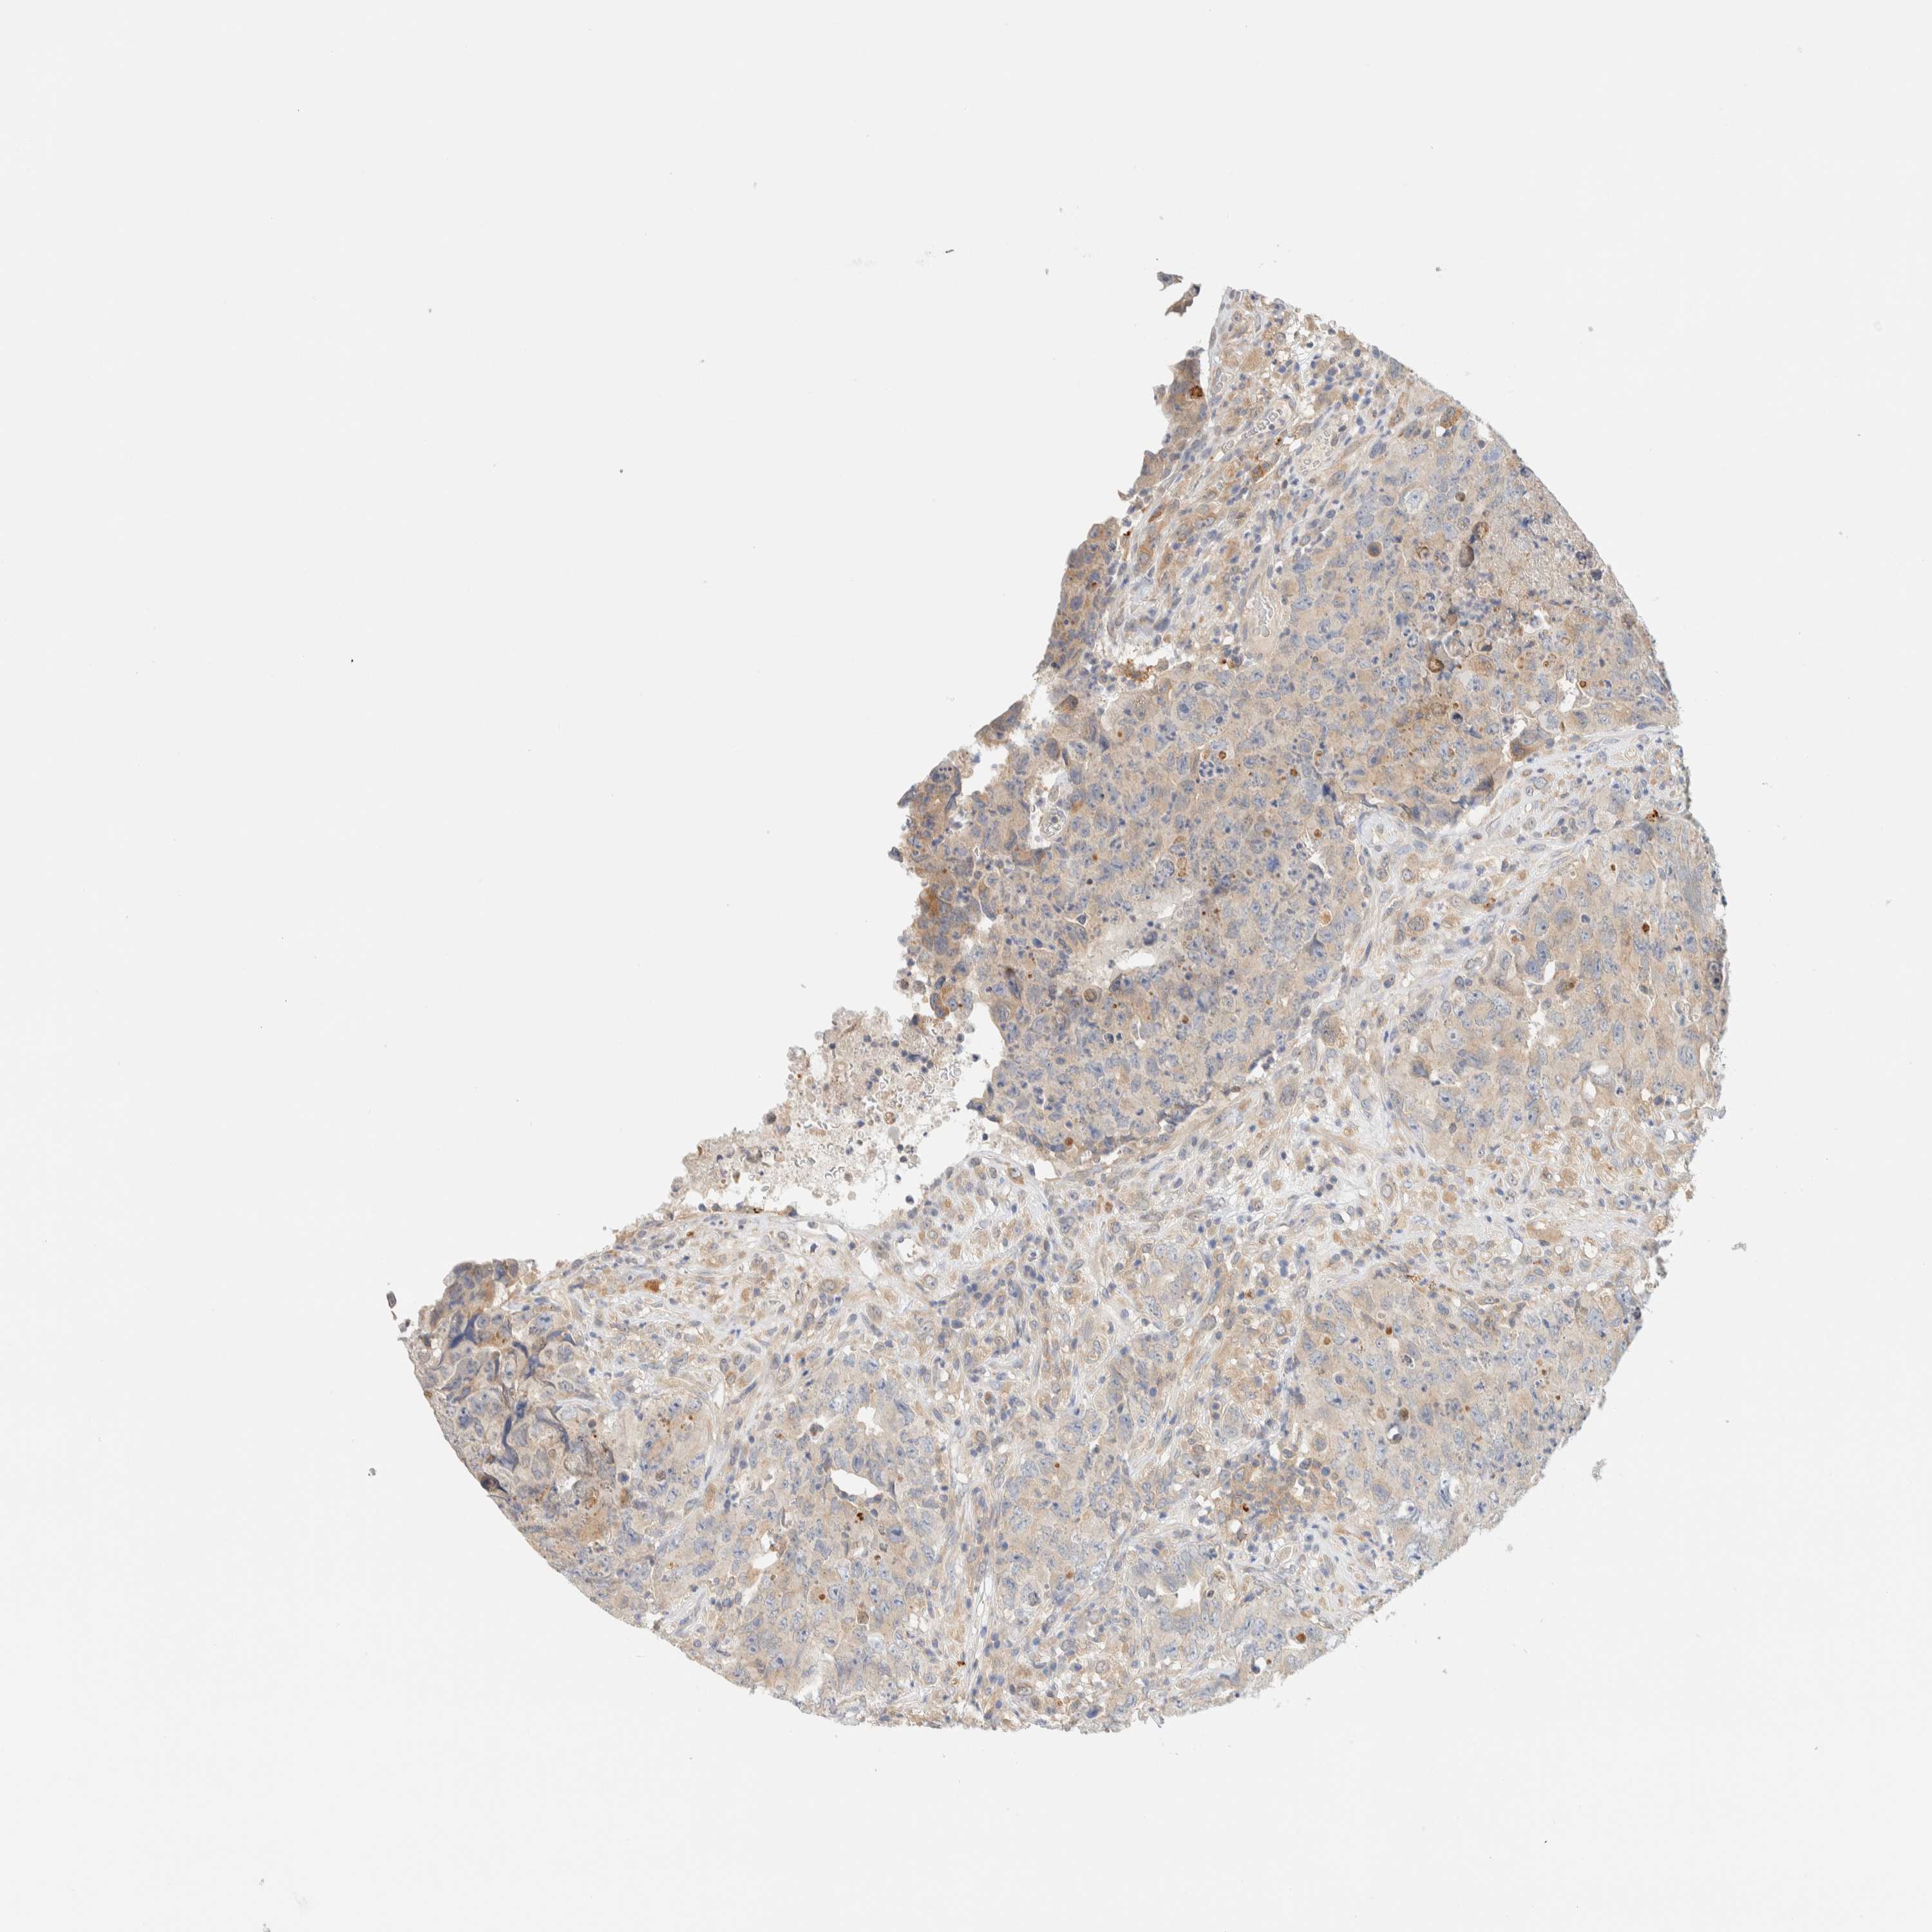

TESTIS CANCER - Protein expressioni

A mouse-over function shows sample information and annotation data. Click on an image to view it in a full screen mode. Samples can be filtered based on level of antibody staining by selecting one or several of the following categories: high, medium, low and not detected. The assay and annotation is described here.

Note that samples used for immunohistochemistry by the Human Protein Atlas do not correspond to samples in the TCGA dataset.

Antibody stainingi

Antibody staining in the annotated cell types in the current human tissue is reported as not detected, low, medium, or high, based on conventional immunohistochemistry profiling in selected tissues. This score is based on the combination of the staining intensity and fraction of stained cells.

Each image is clickable and will lead to virtual microscopy that enables deeper exploration of all samples and also displays staining intensity scores, fraction scores and subcellular localization as well as patient and tissue information for each sample.

Antibody HPA021581

Antibody HPA023632

Staining

High

Medium

Low

Not detected

Intensity

Strong

Moderate

Weak

Negative

Quantity

>75%

75%-25%

<25%

None

Location

Nuclear

Cytoplasmic/membranous

Cytoplasmic/membranous,nuclear

Carcinoma, Embryonal, NOS

Seminoma, NOS